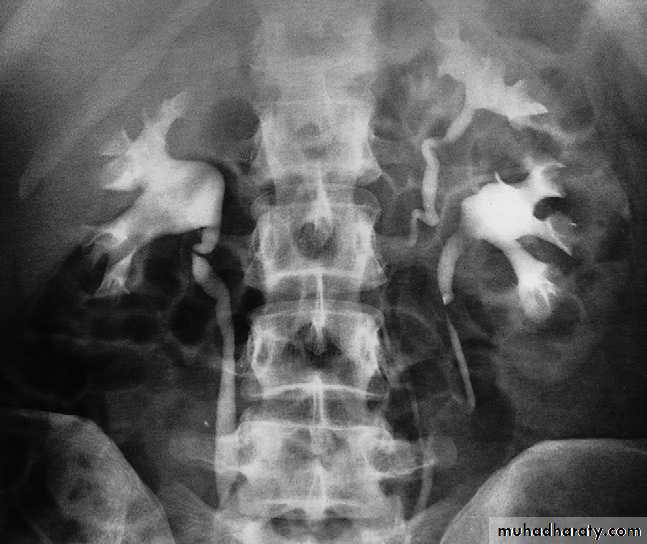

Bifid collecting systems are the most frequent congenital variations. The condition may be unilateral or bilateral. The two ureters may join at any level between the renal hilum and the bladder or may insert separately into the bladder.The ureter draining the upper moiety may drain outside the bladder, e.g. into the vagina or urethra, producing incontinence if the opening is beyond the urethral sphincter. Such ureters, known as ectopic ureters, are frequently obstructed and lead to dilatation of the entire moiety; the dilated lower ureter may prolapse into the bladder, forming a ureterocele. The ureterocele causes a smooth filling defect in the bladder on IVU, and on ultrasound may be seen as a cystic structure within the bladder at the position of the vesicoureteric junction.